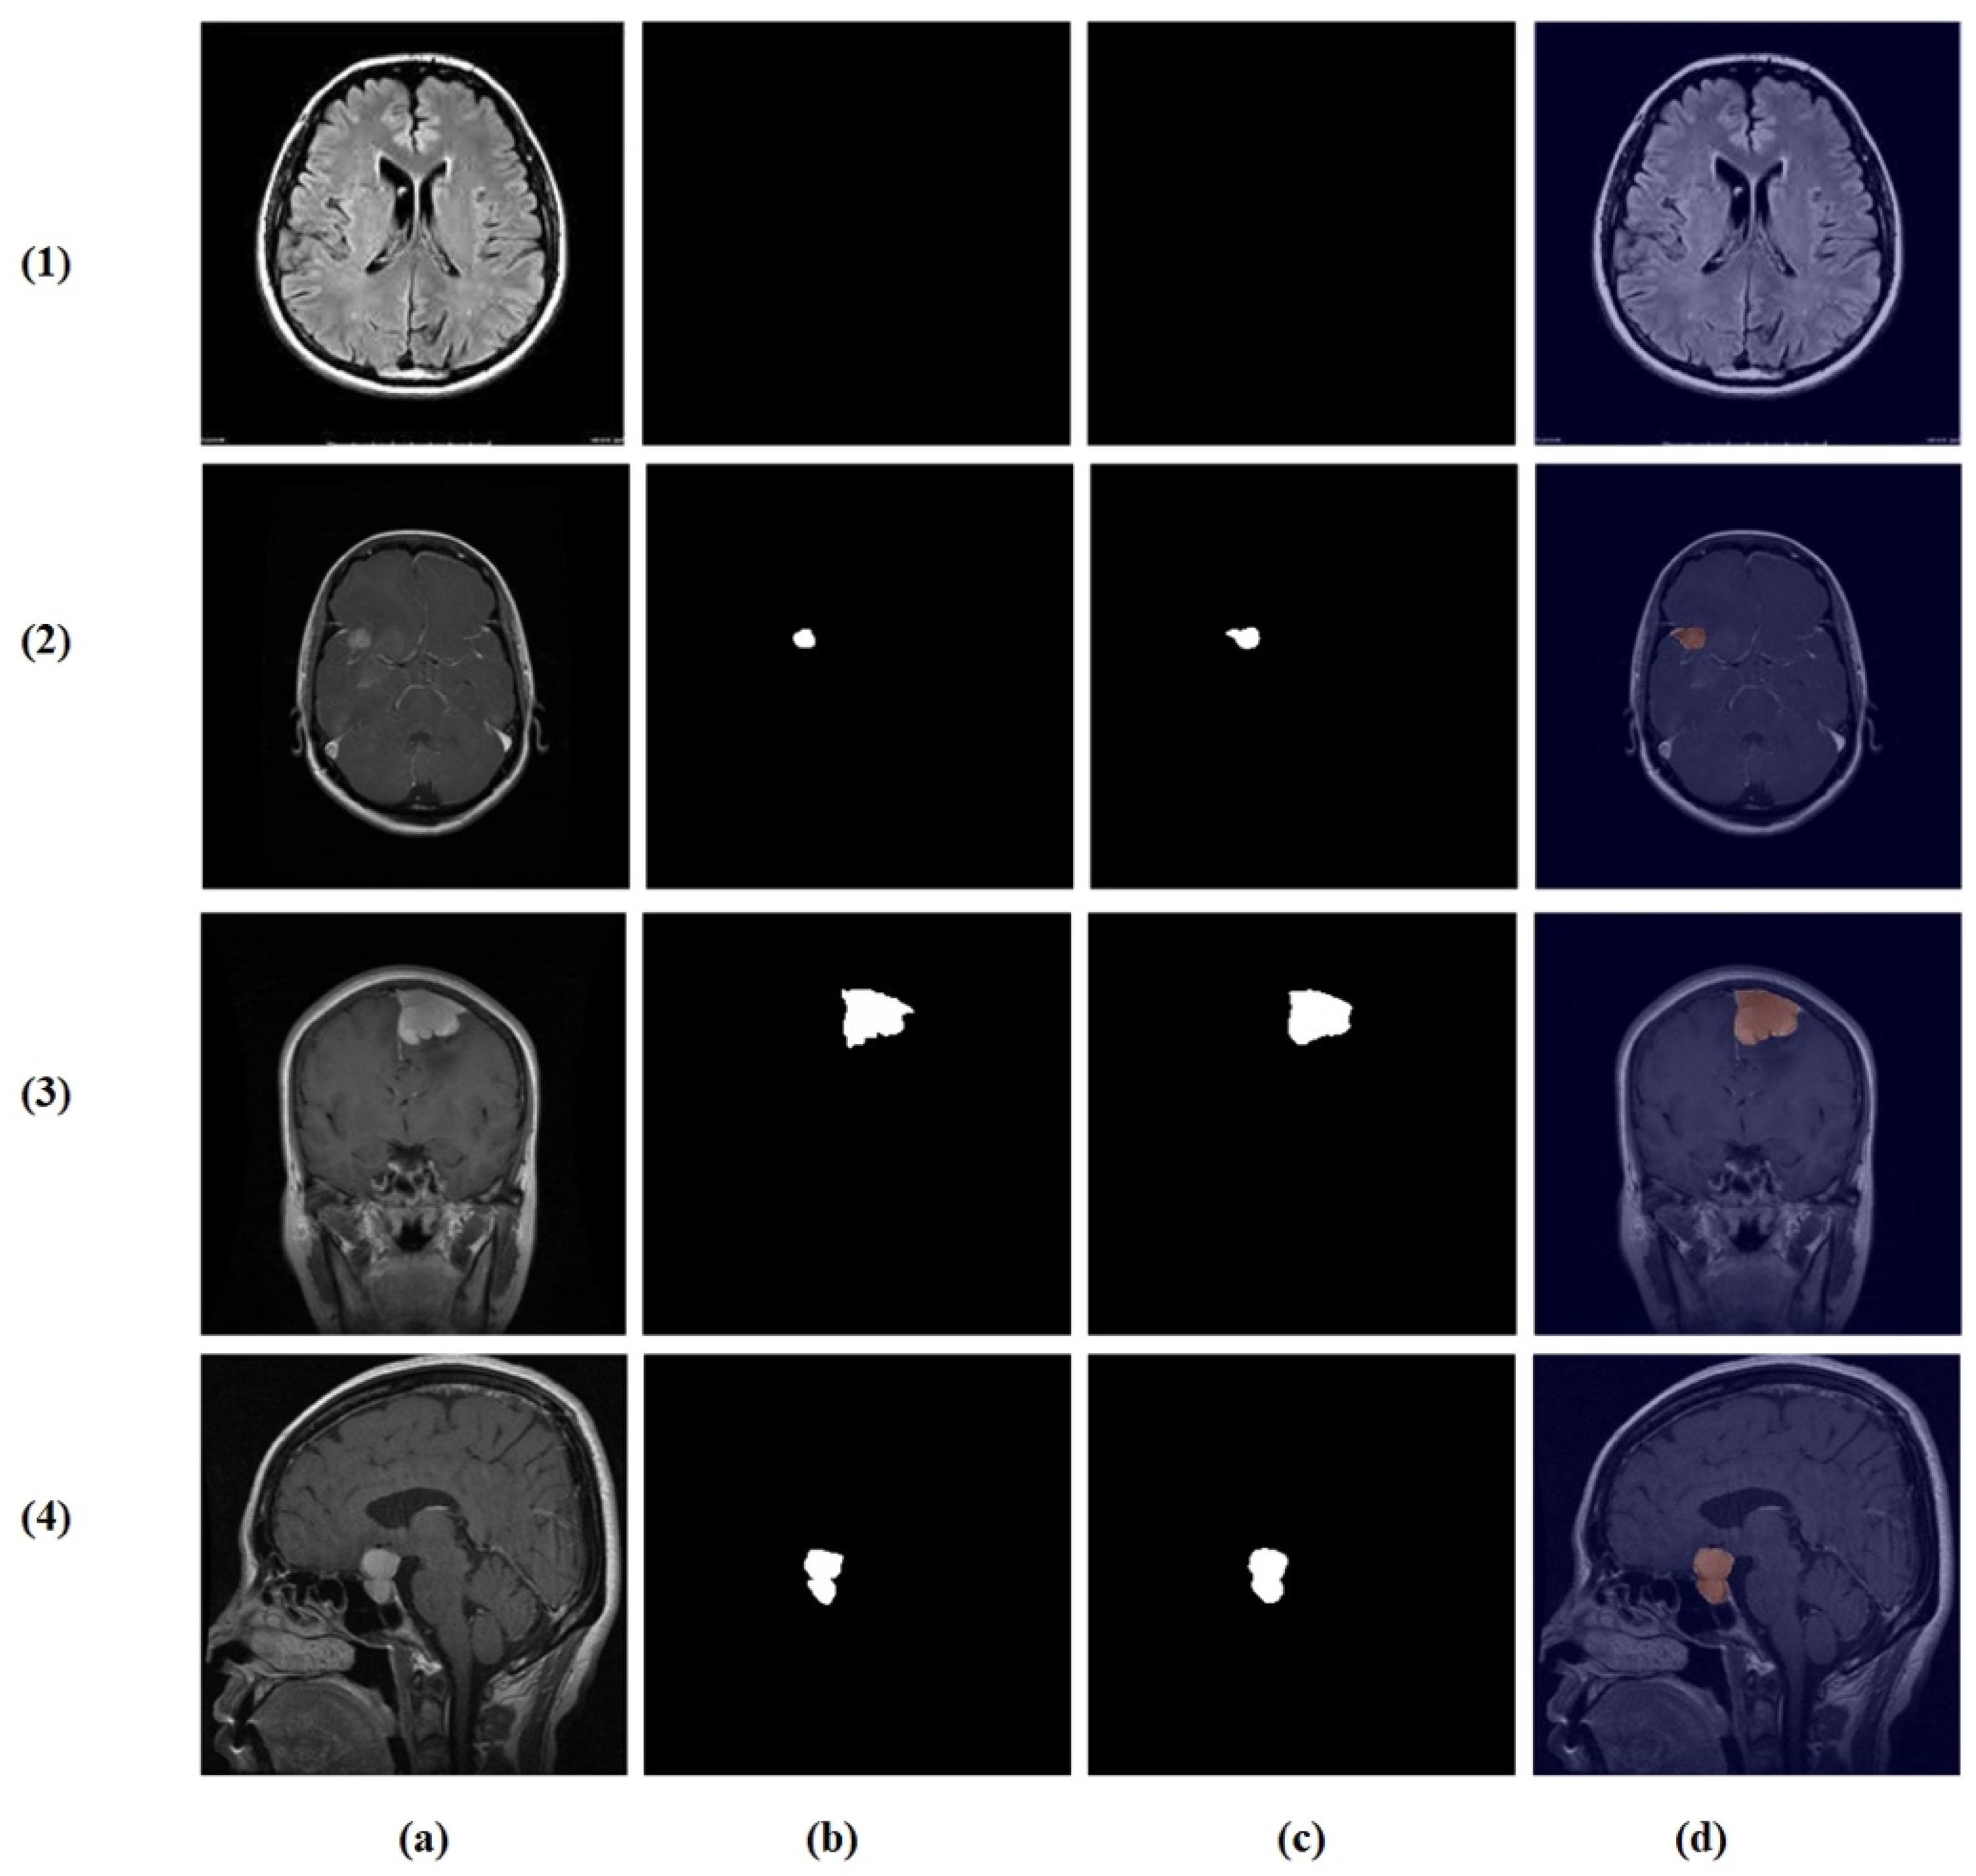

Visual inspection of the segmentation outputs (Figure 10) demonstrates the model’s capability to accurately delineate tumor boundaries across diverse tumor types and imaging conditions. The model successfully handles variations in tumor size, shape, and location, producing precise segmentation masks that closely align with ground truth annotations.

Figure 10.

Random test set predictions. Columns: (a) input image, (b) ground truth mask, (c) predicted mask, and (d) overlay. Rows (true → predicted): (1) no tumor → no tumor, (2) glioma → glioma, (3) meningioma → meningioma, and (4) pituitary → pituitary.

While the model demonstrates strong overall performance, certain challenging cases remain difficult. As shown in Figure 11, these include misclassification between glioma and meningioma (row 1) and under-segmentation of tumors with faint boundaries (row 2). Such failures typically occur when tumors exhibit overlapping intensity profiles, low contrast with surrounding tissue, or ambiguous morphological features.

Figure 11.

Challenging test set cases. Columns: (a) input image, (b) ground truth mask, (c) predicted mask, and (d) overlay. Rows (true → predicted): (1) glioma → meningioma (misclassification) and (2) pituitary tumor with under-segmentation.